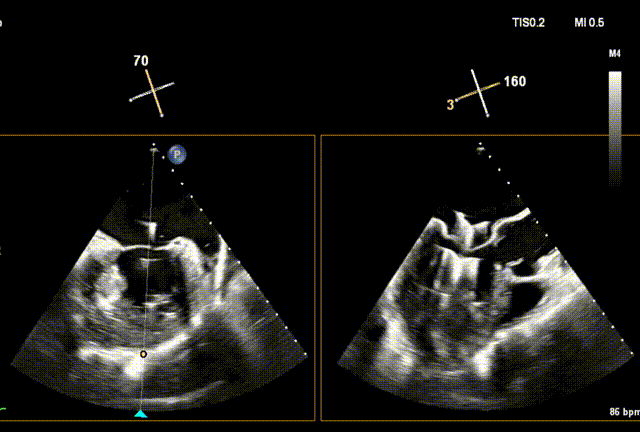

术后Xplane彩色图像

夹合后二尖瓣反流量0+,平均跨瓣压差3mmHg